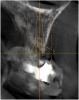

Fig. 4 The implants had to be placed in limited bone and avoid the mandibular nerve. The most predictable way to get the maximum number and size implants was with a virtual plan and surgical guide.